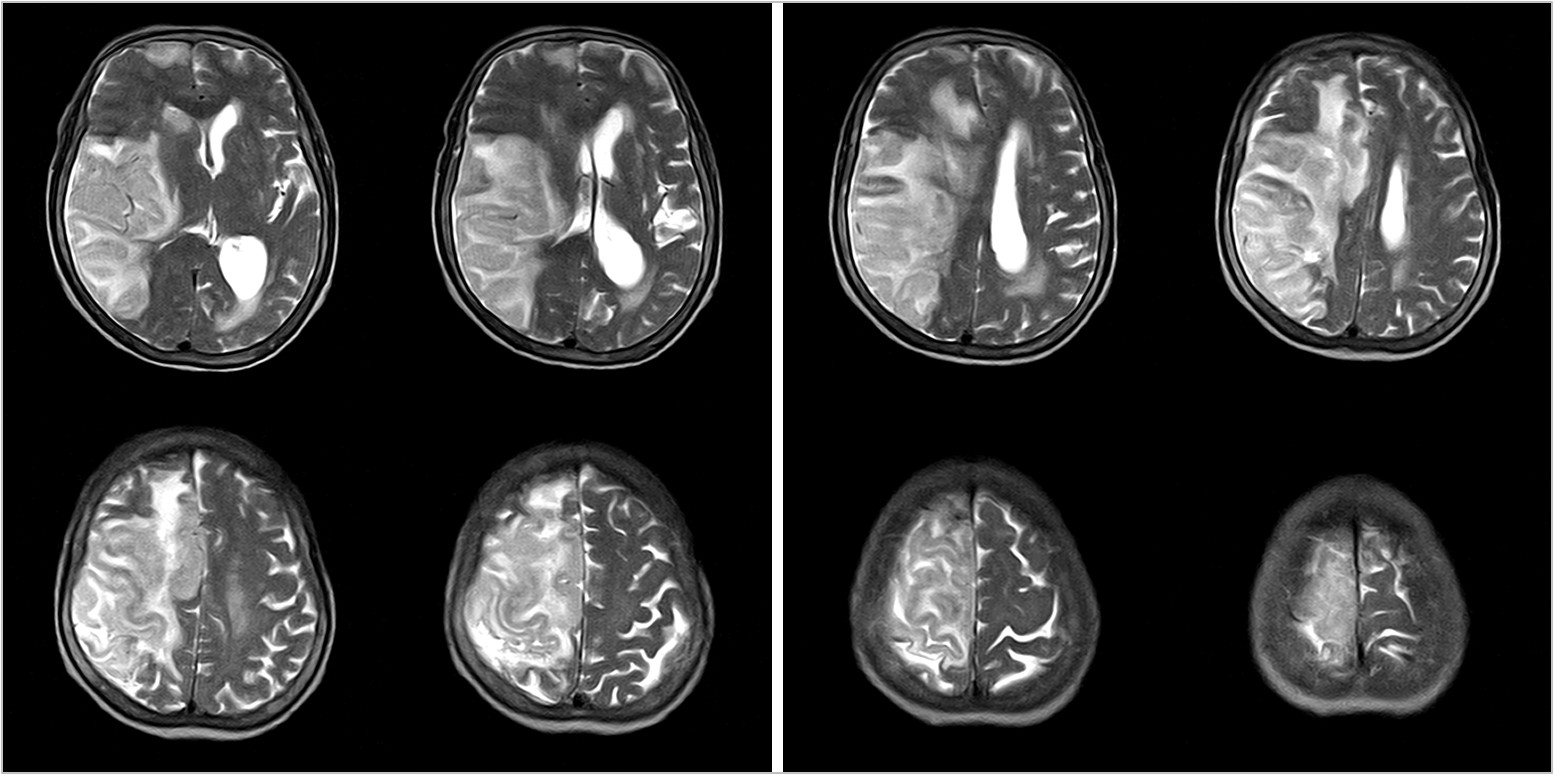

Hình ảnh lâm sàng